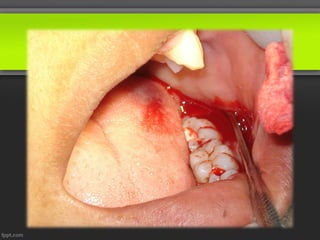

5)Colgajo con Descarga hacia mesial de la 2MI.

6)Ostectomía con fresa quirúrgica redonda grande para la

eliminación del hueso.

COLGAJO CON DESCARGA MESIAL

OSTEOTOMIA